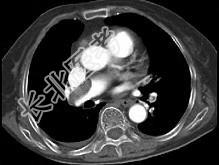

- 单项选择题82岁,女性, 突发右侧胸痛,呼吸急促, 行急诊CT检查,如图所示, 请选择最佳答案 ( )

D、肺动脉栓塞